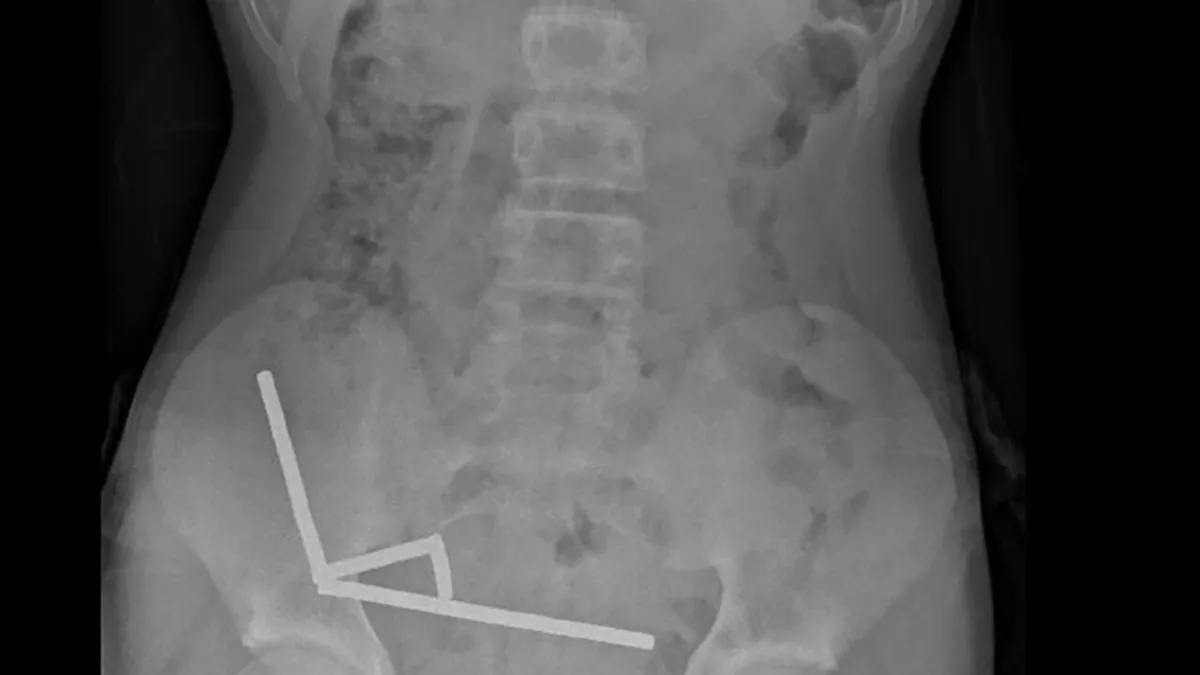

This undated handout released on October 24, 2025 from the New Zealand Medical Journal (NZMJ) shows an x-ray image of pieces of high-power magnets clumped up in the intestines of a New Zealand teenager in Tauranga. Handout / NEW ZEALAND MEDICAL JOURNAL (NZMDJ)/AFP

A 13-year-old boy in New Zealand swallowed up to 100 high-power magnets he bought on Temu, forcing surgeons to remove tissue from his intestines, doctors said on Friday.

"He disclosed ingesting approximately 80–100 5x2mm high-power (neodymium) magnets about 1 week prior," said a report by hospital doctors in the New Zealand Medical Journal.

An X-ray showed the magnets had clumped together in four straight lines inside the child's intestines.

"These appeared to be in separate parts of bowel adhered together due to magnetic forces," they said.